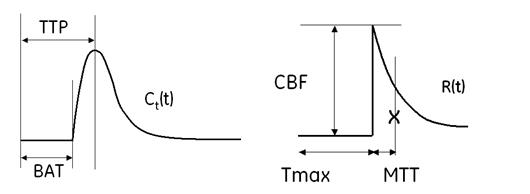

Time to Peak

Time To Peak is inversely related to CBF in which reduction of blood flow results in an increase in the time needed for the contrast to reach its peak in brain tissue.

Bolus Arrival Time

Bolus Arrival Time (BAT): time from scan start to tracer bolus arrival of bolus at tissue.

Tmax

Time to maximum value of Residue function (Tmax). This represents the tracer delay effect at a pixel.